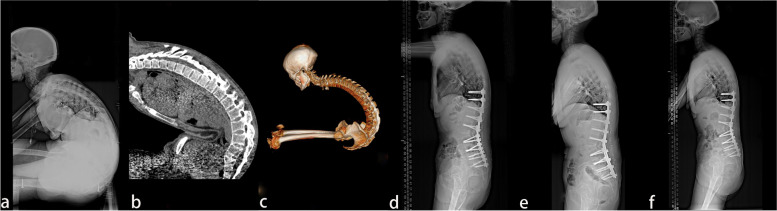

A total of 38 patients with AS combined with thoracolumbar kyphosis were successfully treated by PSO, with a mean follow-up time of 26.9 ± 11.9 months. There were 30 males and 8 females with a mean age of 41.6 ± 7.1 years. Twenty patients consisted in the lumbar lordosis group and 18 patients in the lumbar kyphosis group, with a mean operation time of 289.4 ± 123.2 min and 267.8 ± 96.8 min (P > 0.05), respectively. The patients were further subdivided into the lumbar lordosis T12 group (Fig. 1) with 11 patients, the lumbar lordosis L1 group (Fig. 2) with 9 patients, the lumbar kyphosis L2 group (Fig. 3) with 10 patients, and the lumbar kyphosis L3 group (Fig. 4) with 8 patients.

Fig. 4.

A 46-year old female patient. a, b, c The preoperative X-ray and 3-D CT reconstruction showed that the parietal vertebrae were located at T11/T12, which belonged to the lumbar kyphosis group. d Smith-Petersen osteotomy was conducted at L1–L2, L4–L5, and L5–S1, together with single-segment pedicle subtraction osteotomy (PSO) at L3. Lumbar lordosis, global kyphosis, and sagittal vertical axis improved from the preoperative 44°, 105°, and 257.39 mm to –44°, 53° and 55.47 mm, respectively. e) One-year post-operation, lumbar lordosis, global kyphosis, and sagittal vertical axis were –45°, 60°, and 47.53 mm, respectively. f) At the last follow-up at the 37th-month post-operation, no apparent orthopedic loss was observed, and lumbar lordosis, global kyphosis, and sagittal vertical axis were –47°, 61°, and 48.56 mm, respectively

Via previous articles [1, 5, 8], double-segment PSO or PSO combined with Smith-Petersen osteotomy (SPO) was recommended to treat patients with severe kyphosis (> 60°) to obtain a stable sagittal balance. In the present study, a 46-year-old male (Fig. 4) with a typical "folded knife dorsum" preoperatively possessed a CBVA of –60°, and an SVA of 257.39 mm combined with lumbar lordosis (LL > 45°). Preoperatively, the required osteotomy angle was calculated to be 86.5°, and SPO combined with PSO was performed. Briefly, SPO was conducted at L5–S1, L4–L5, L1–L2, and PSO osteotomy at L3, respectively, combined with internal fixation of T9–S1 vertebrae. In our cohort, postoperative CBVA, LL, GK, and SVA were greatly improved. In one postoperative year, a satisfactory spinal sagittal balance with good function recovery was received.